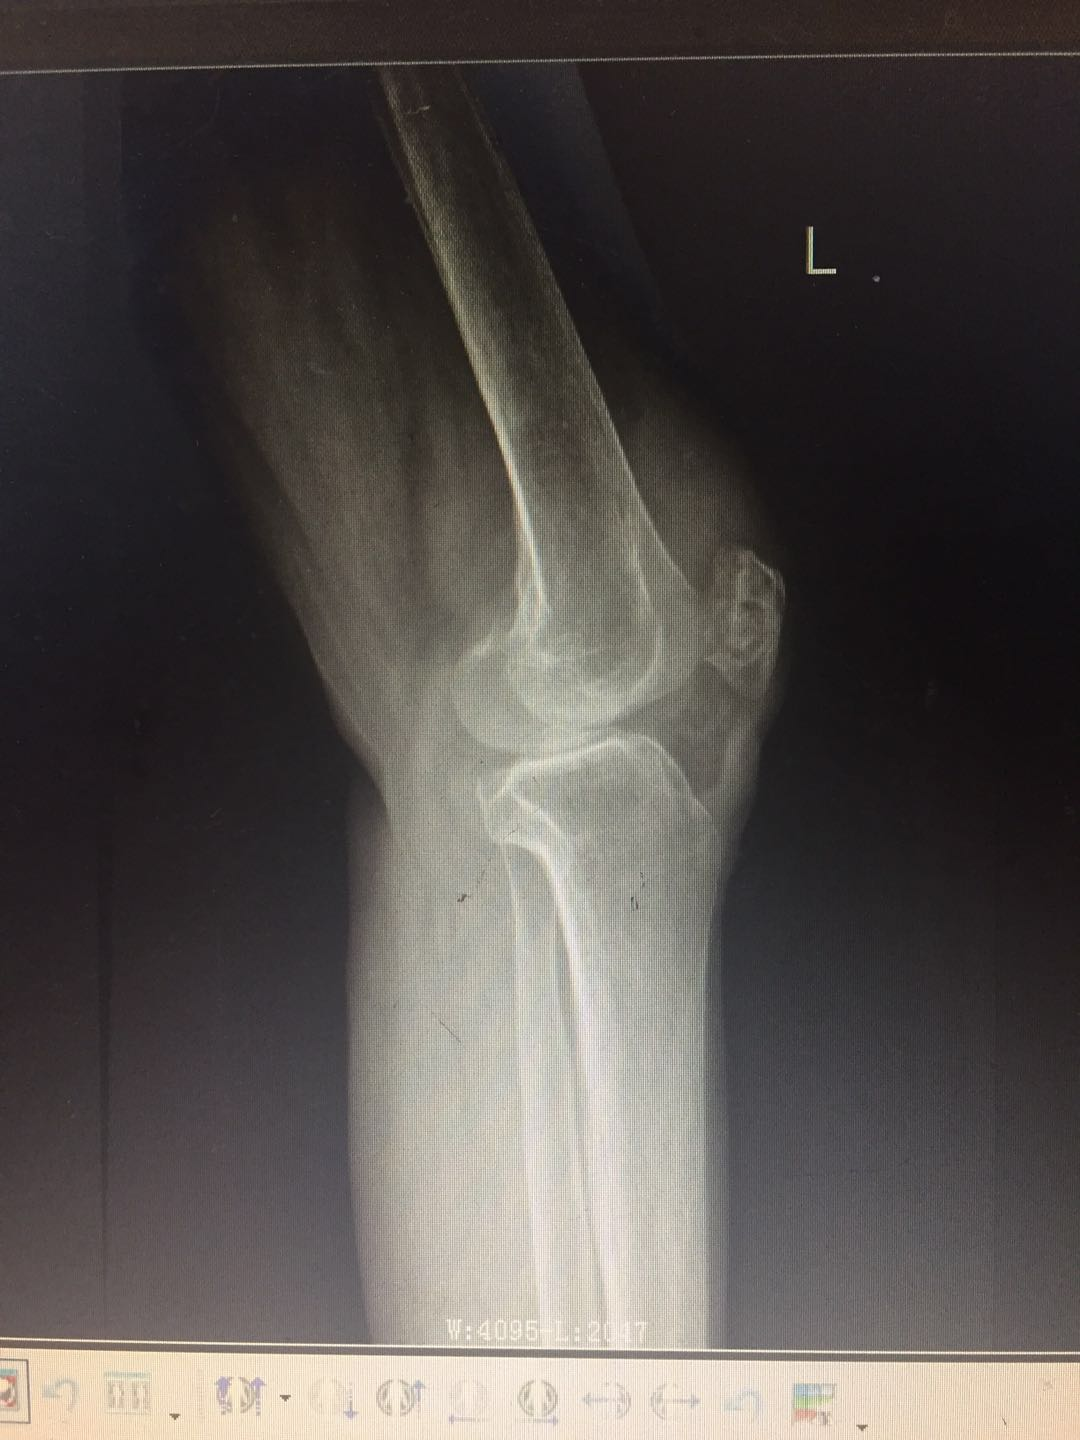

患   者:阳某,男,58岁。

主   诉:因左胫骨骨折术后伤口流脓5年,入院治疗。

现病史:自诉5年前因车祸致左小腿上段疼痛伴活动受限,在当地医院诊断为“左胫骨上段粉碎性骨折”,并行骨折切开复位内固定术,术后伤口未完全愈合,持续流出脓性液体,予伤口间断换药处理,伤口可愈合,但间断出现破溃口,其内流出脓液,现就诊于我院。

专科检查:左小腿中上段前外侧可见长约15cm纵行手术疤痕,周围部分皮肤色素沉着,可见两处皮肤溃口,挤压有脓性分泌物流出,皮下可扪及条状硬物,轻压痛,无异常活动,肢端血运感觉尚可。

辅助检查:血生化检查:血常规示白细胞12.35*109/L,血沉40mm/h,CRP正常,余未见明显异常。

影像资料:

诊       断:

右胫骨上段慢性骨髓炎;右胫腓骨陈旧性骨折伴胫骨骨折术后内固定物滞留。